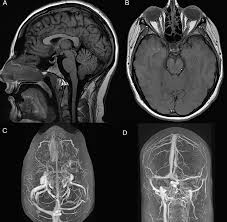

Talk to our Chatbot to narrow down your search. However endocrine evaluation strongly suggests a pituitary origin. No mass or other significant findings were noted Fig 1A and B.

Heinen Bros Ag Empty Sella Syndrome And Weight Gain. The coexistence of a cervical meningioma rises the hypothesis of an ectopic ACTH syndrome. Could Empty Sella Syndrome cause you to loose weight and also prevent you putting weight on - I am a 59 yr old male previously to being diagnosed with ess I had back pain which after an ct. Unfortunately these types of endos are not everywhere and tend to hang out at larger medical centers that have a pituitary program. Check the full list of possible causes and conditions now. Arnab Maji General Family Physician. Talk to our Chatbot to narrow down your search. Sagittal and coronal MR images showed a partial empty sella. When you gain weight despite eating very little.